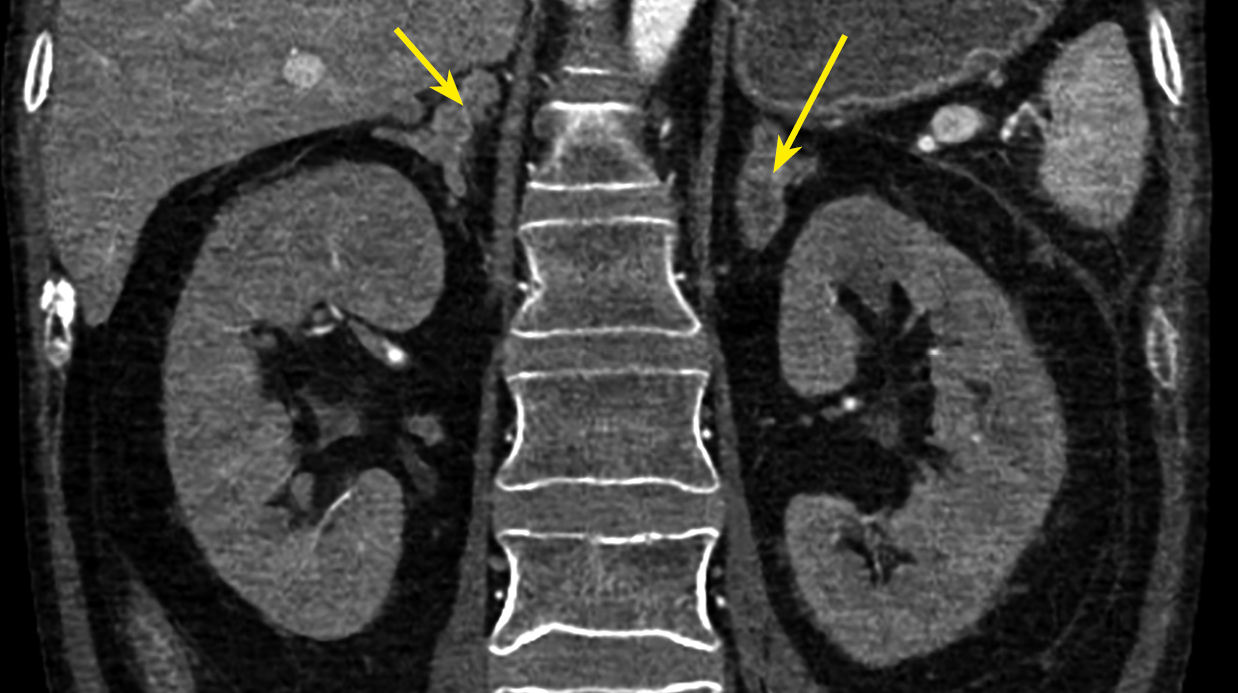

При КТ грудной клетки свежих инфильтративных изменений не выявлено. В S3 левого легкого — уплотнение легочной ткани вытянутой формы — 2,5х1,8 см, накапливающее контрастное вещество (рис. 3). Лимфоузлы легких и корней легких не увеличены, структурно не изменены.

Рисунок 3. КТ органов грудной клетки: в S3 левого легкого уплотнение легочной ткани вытянутой формы — 2,5х1,8 см, накапливающее контрастное вещество.

Локальное уплотнение легочной ткани было расценено либо как метастаз опухоли ЩЖ, либо как первичная опухоль легкого. При КТ брюшной полости новообразований не выявлено. Визуализированы признаки пареза кишечника (рис. 4), диффузная гиперплазия обоих надпочечников — толщина правого увеличена до 1,4 см, левого — до 1,6 см (рис. 5). При КТ головного мозга выявлены признаки выраженной атрофии коркового вещества. Область турецкого седла не изменена.

Диагностирован эндогенный гиперкортицизм, АКТГ-эктопированный синдром. Наиболее вероятным источником избыточной продукции АКТГ признавалось визуализированное при КТ новообразование легкого. Другой возможной причиной гиперкортицизма, предположительно, являлась МКЩЖ.